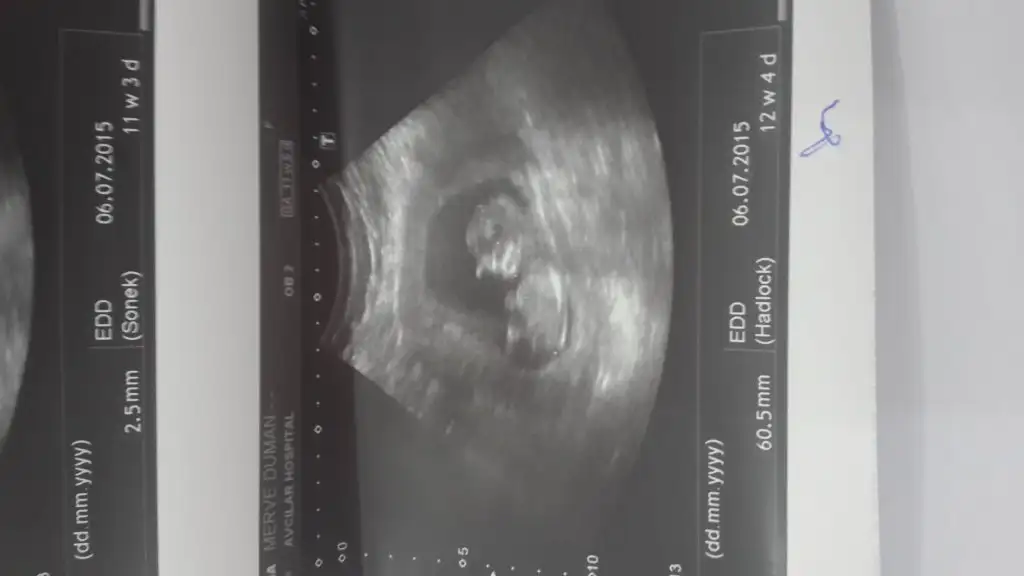

dr soylemeden siz gorun genital nub teorisi ( bebegin cinsiyeti)

Arkadaslar bilen varsa bakabilirmi.? Cok merak ediyorum lütfen.bir arkadaş sadece cvp yazmıs.

buda benim bebişim tahminlerinizi bekliyorum arkadaşlar:anneadayı::nazar:

Kac haftalik erkek gibi gorunuyor